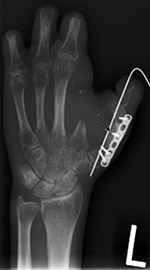

Variable angle volar distal radius locking plate |

20 year-old woman with surgical plate placement for a malunited distal radius fracture. From Taljanovic, 2005 |